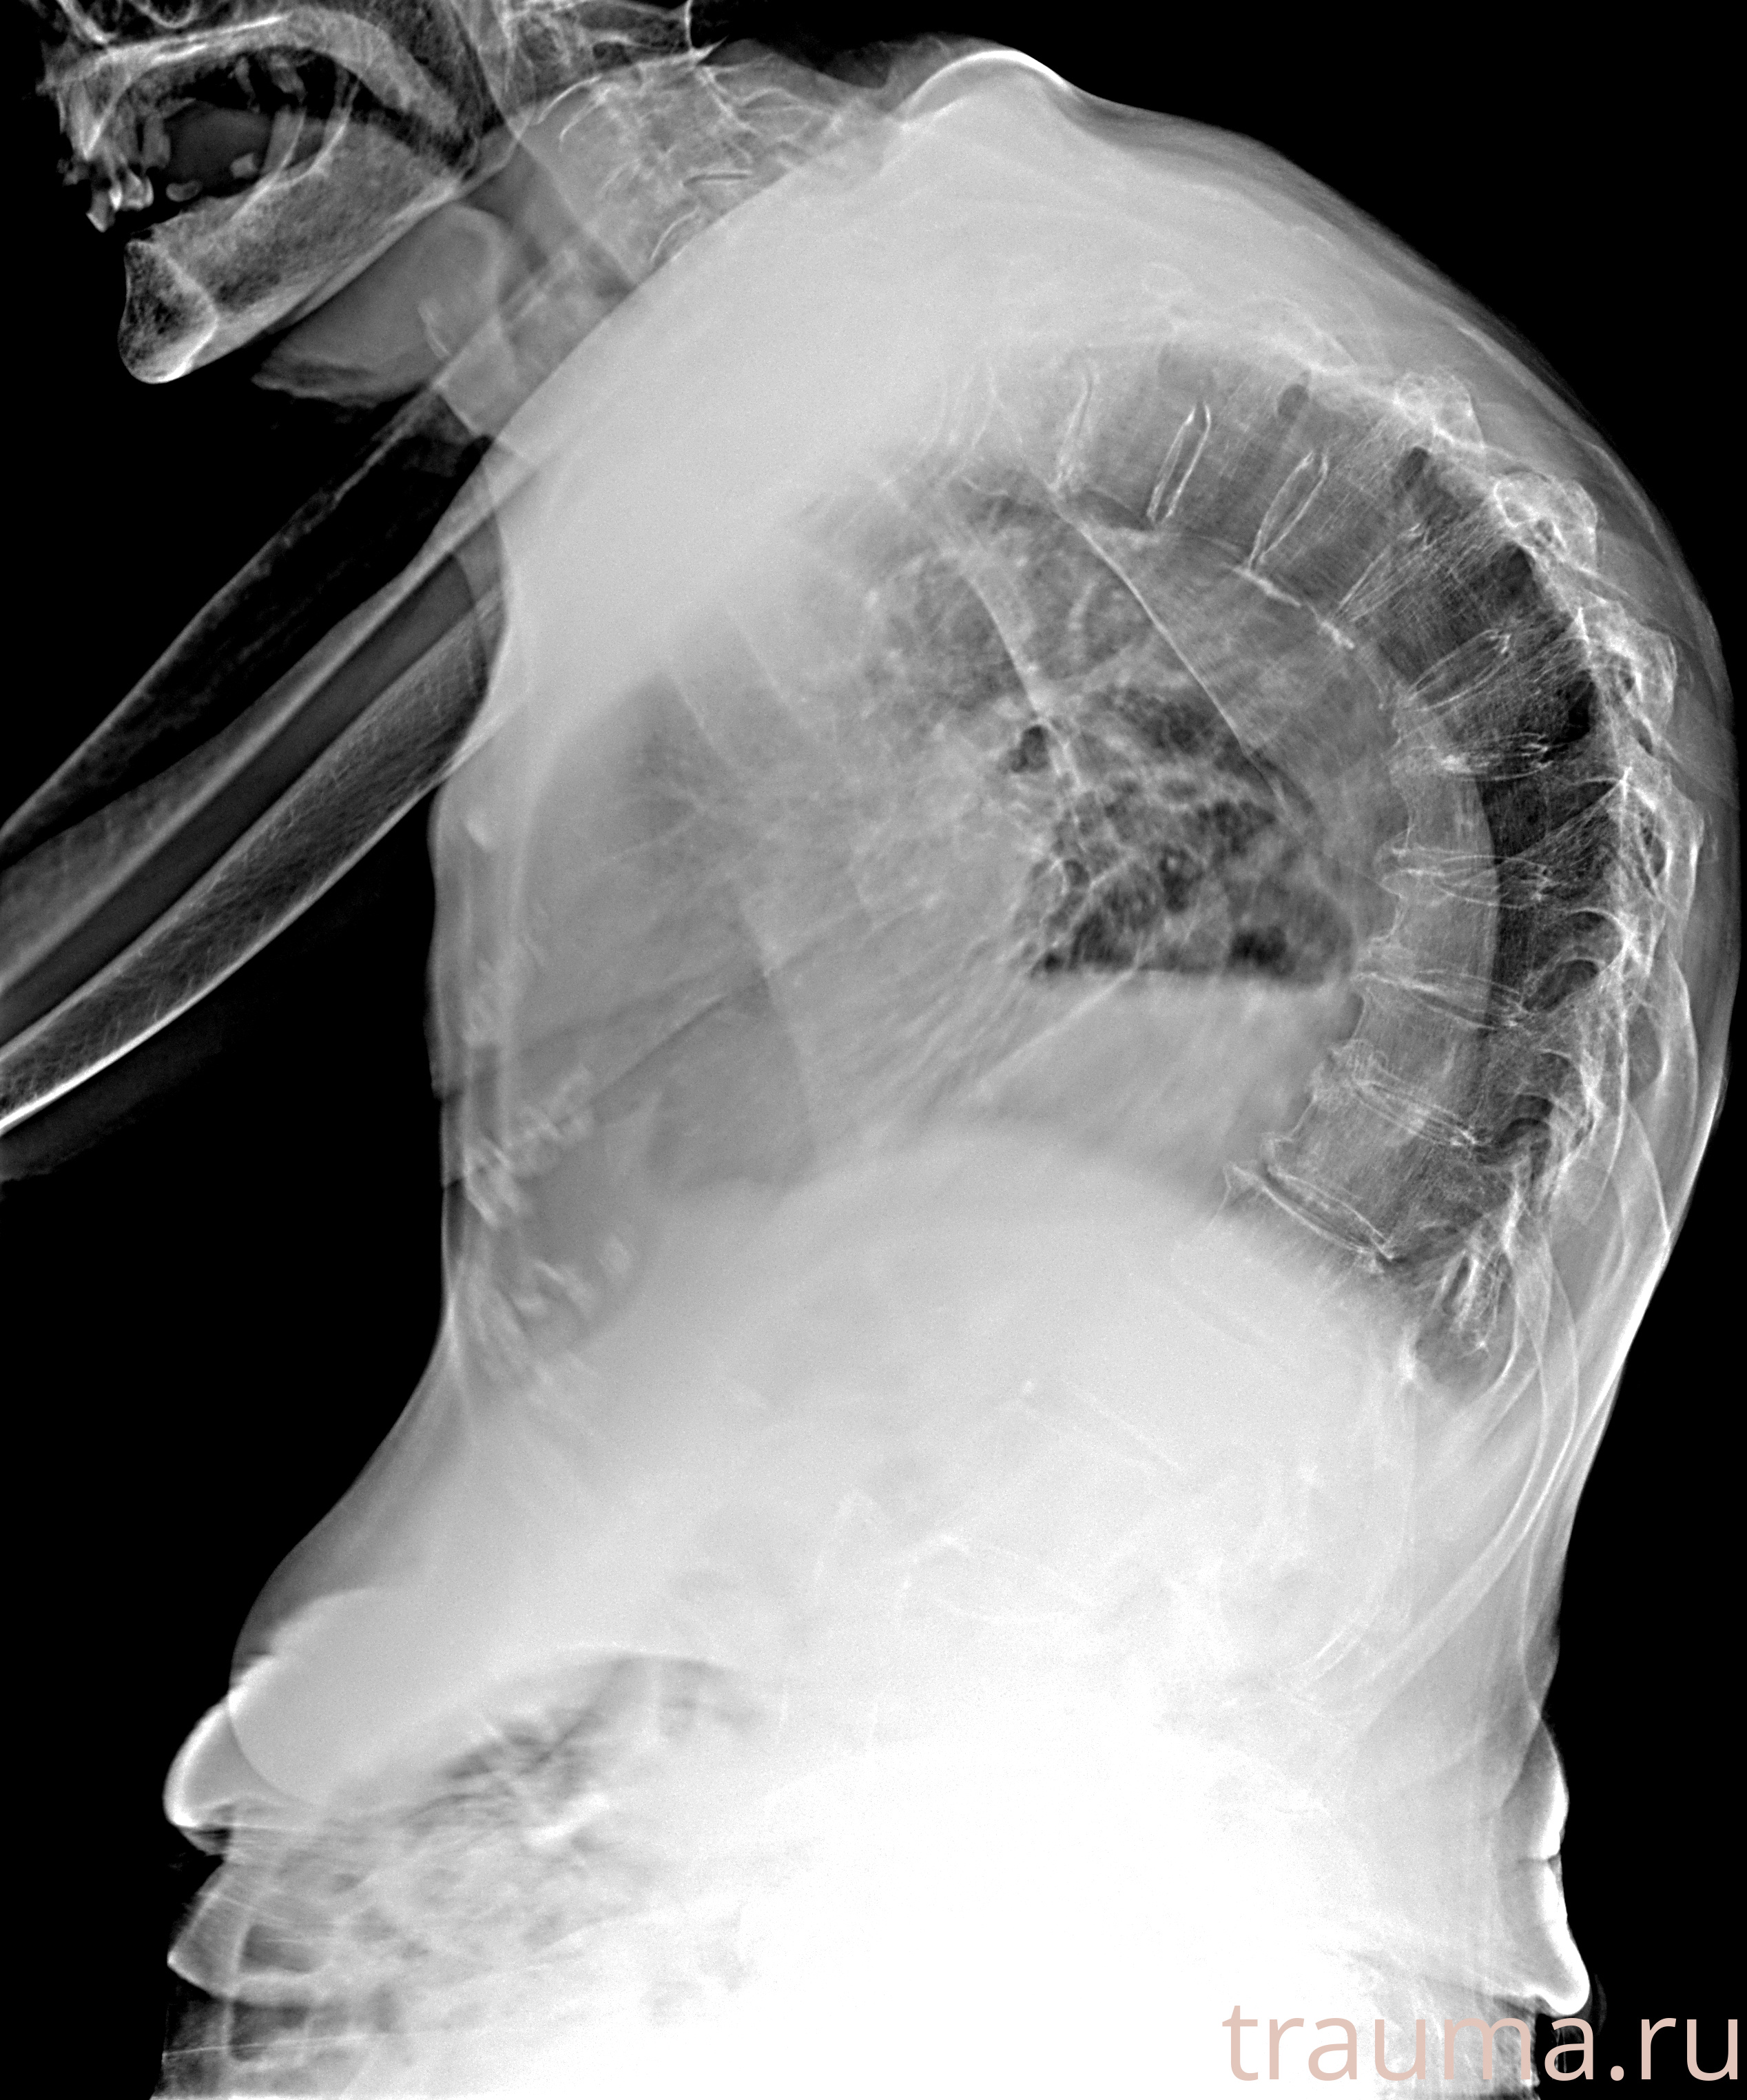

Рентген на дому: по вашему адресу приезжает врач-рентгенолог, травматолог-ортопед с мобильным рентгеновским аппаратом, проводит диагностику травмы или заболевания, делает необходимые рентгенограммы, дает рекомендации по дальнейшему лечению. Получить качественные снимки в домашних условиях возможно благодаря уникальной методике, разработанной МосРентген Центром для института  Склифосовского